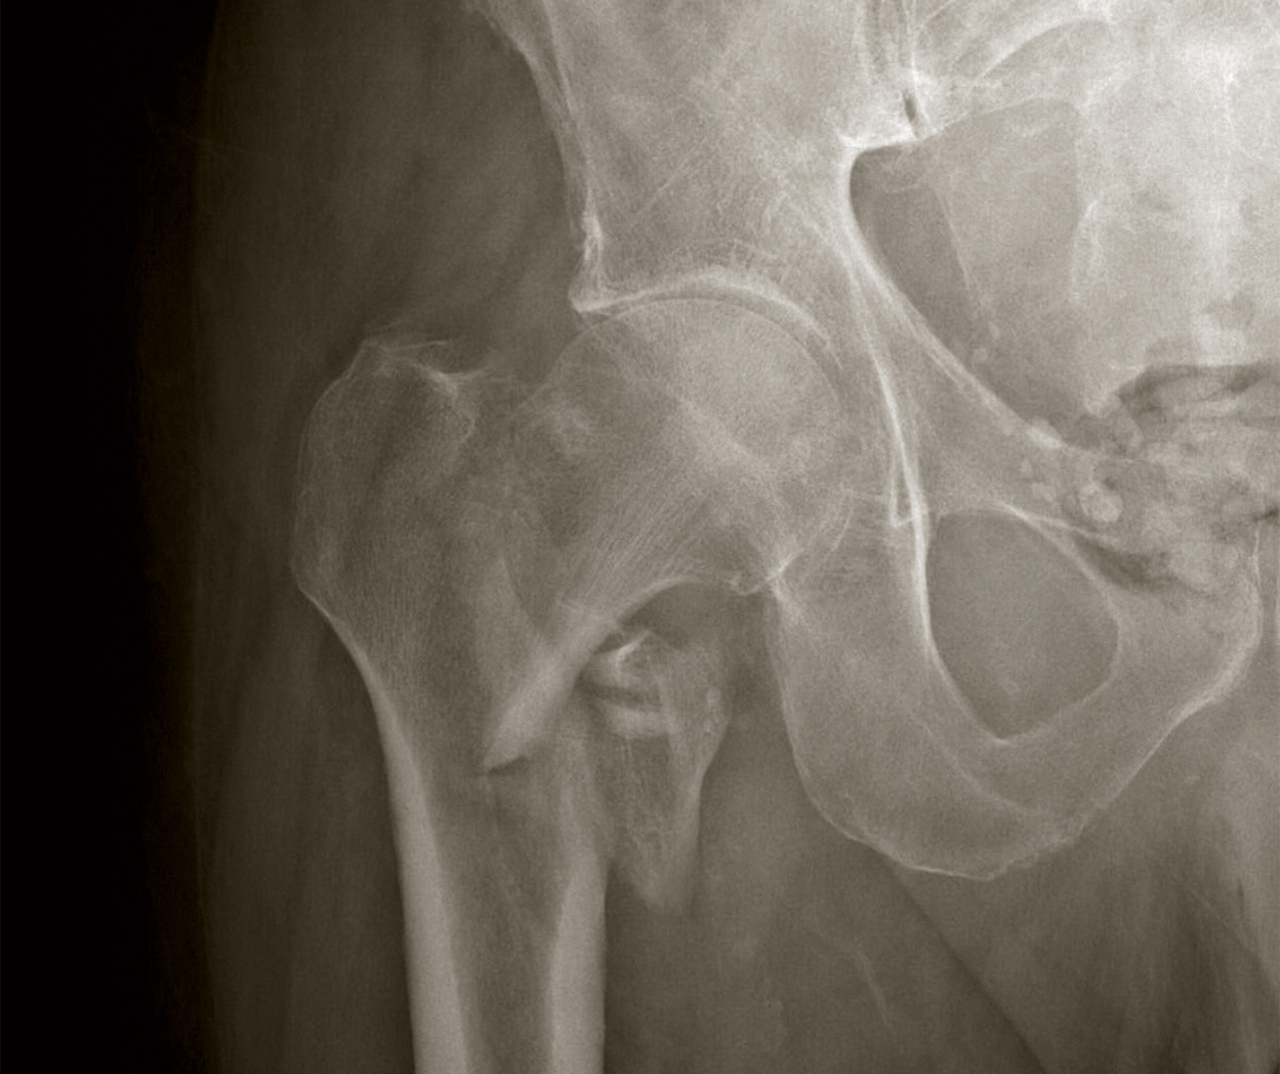

L’imagerie cérébrale est normale. L’hypoglycémie a été corrigée, et la patiente ne se plaint que de sa hanche gauche douloureuse. La radiographie est la suivante.

Figure 2

Question 10 – Quel est votre diagnostic ?